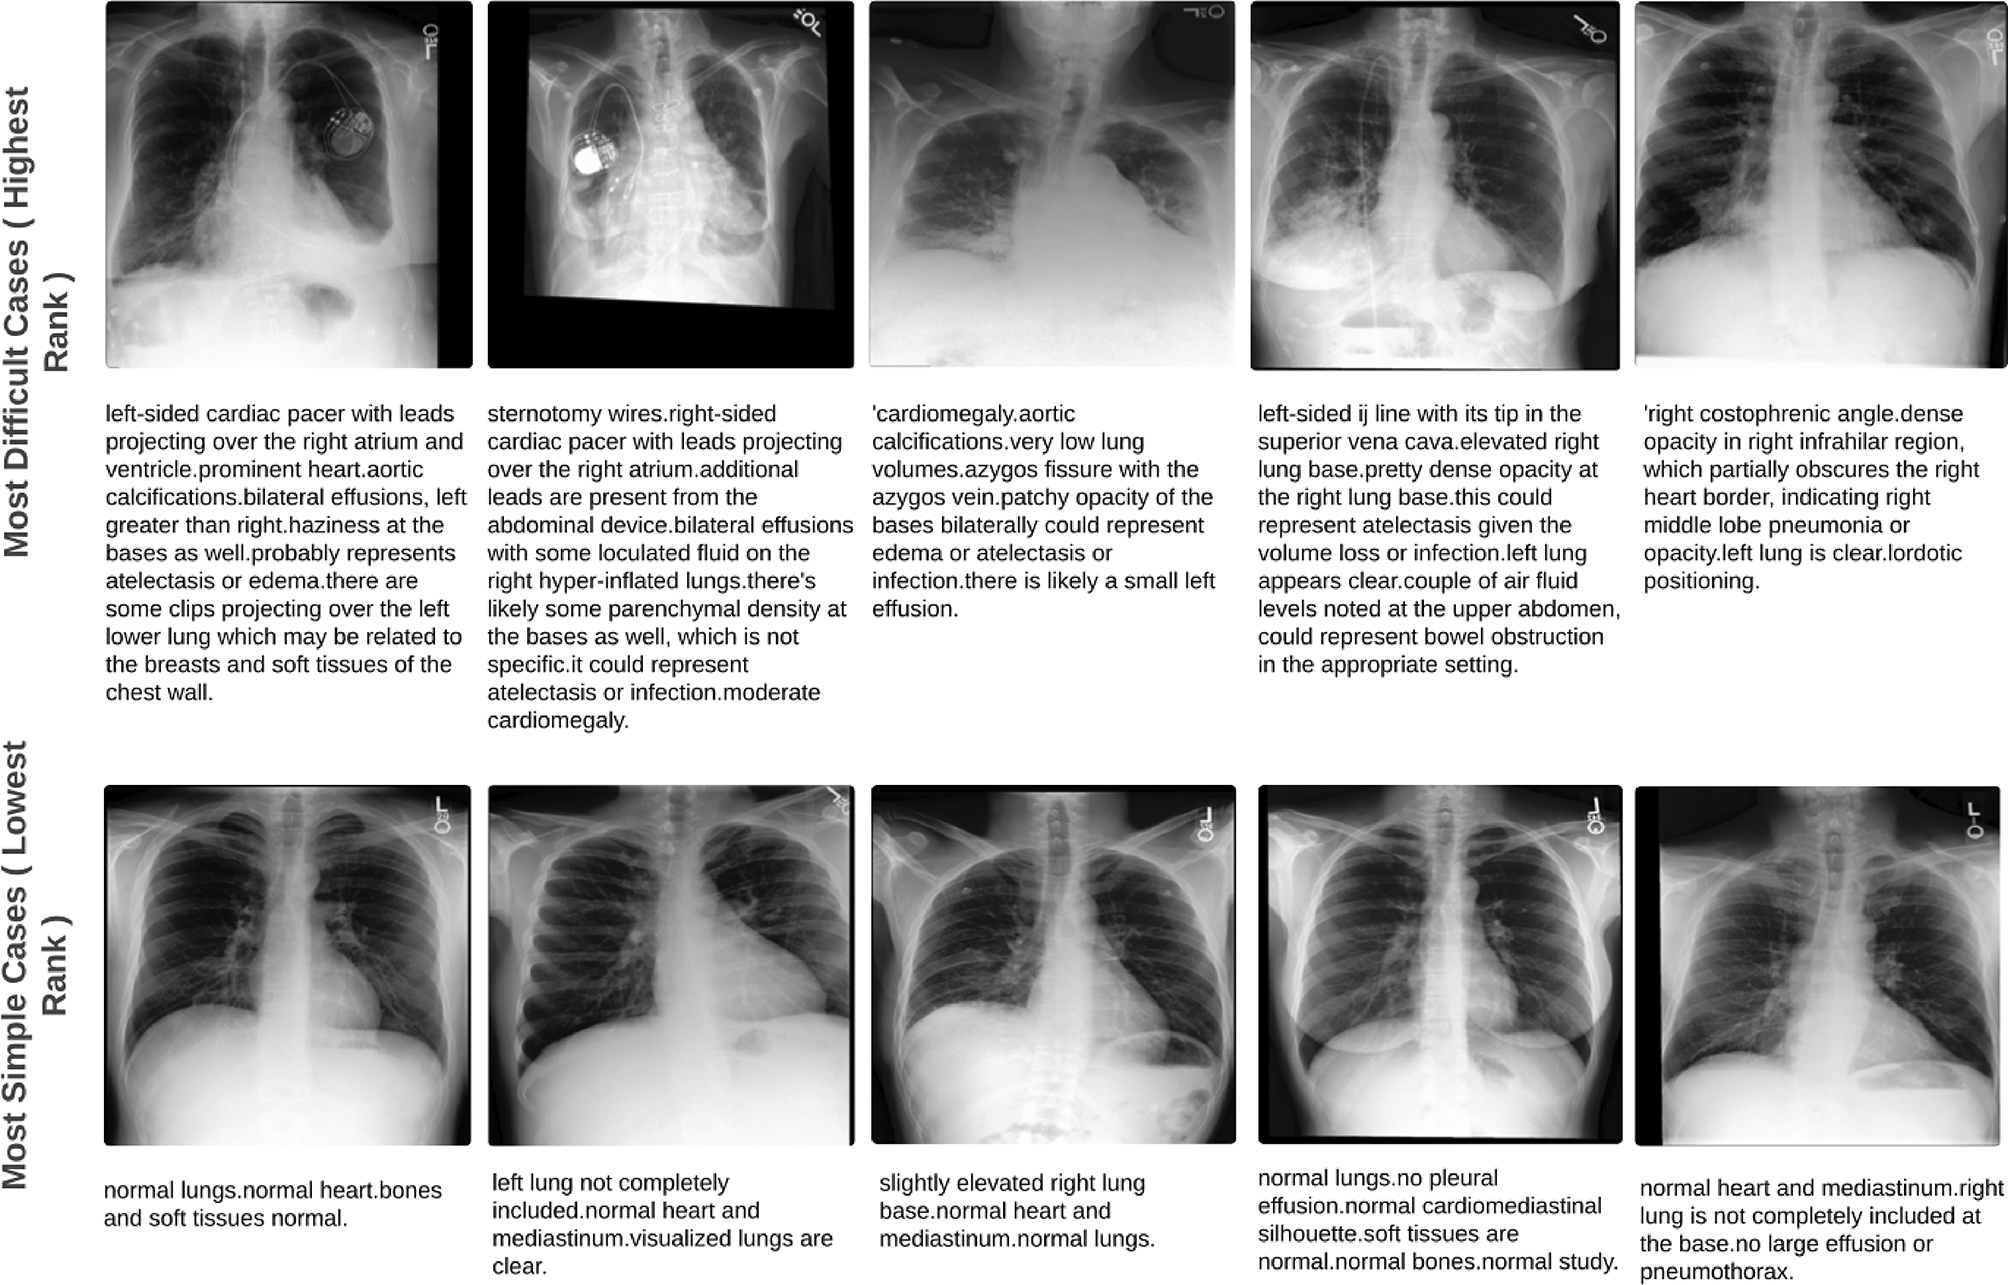

Fig. 6

Examples from the EGD-CXR dataset test set, illustrating the most challenging and simplest cases based on their rank correlations from Fig. 4, Column 2. The first two rows show chest X-ray (CXR) images and corresponding radiology reports for cases ranked highest (most clinical workload), characterized by multiple abnormalities, and requiring longer attention. The third and fourth rows display CXR images and reports for cases ranked lowest (least clinical workload), typically showing no abnormalities or normal findings.